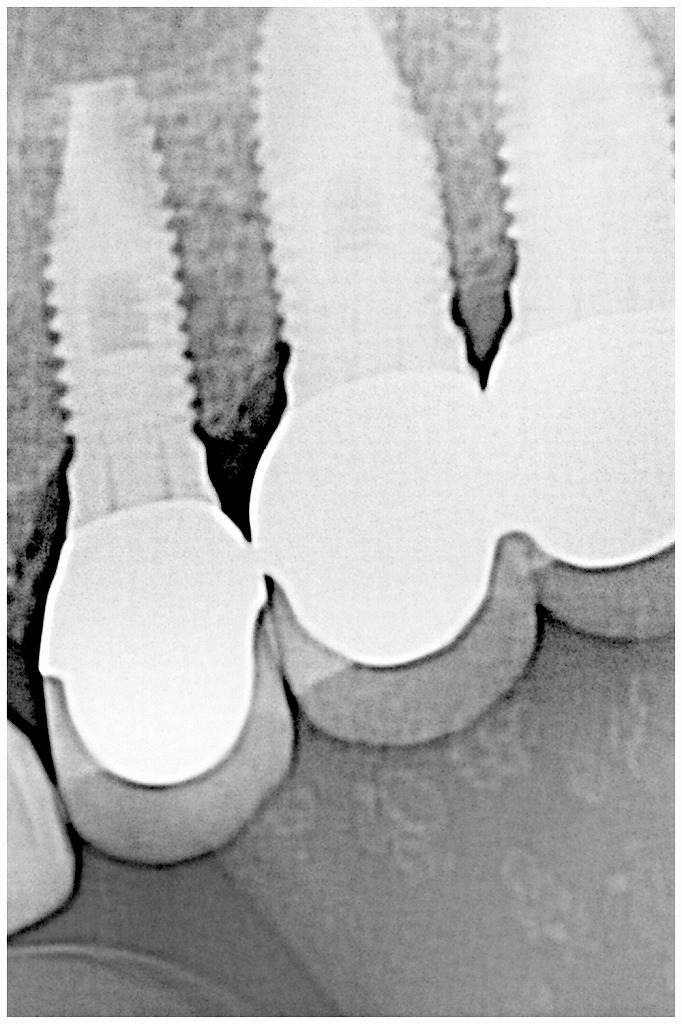

ソケットリフトテクニックにてインプラントを埋入していきます

ここが難関

デンタルレントゲンになります

ソケットリフトを行わないと達成できなかったインプラント埋入になります